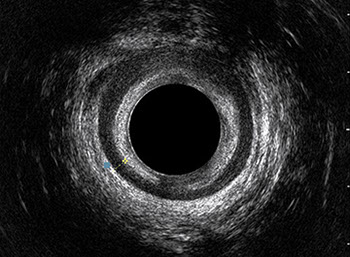

L’ecografia transanale è un esame diagnostico per immagini che consiste nell’introduzione di un trasduttore ad ultrasuoni. Le immagini qualitativamente migliori del canale anale sono ottenute usando un trasduttore rotante, montato in un manipolo rigido, che fornisce un’immagine a 360°. Con le apparecchiature più moderne è anche possibile ottenere immagini tridimensionali.

L’ecografia transanale permette di distinguere la sottomucosa che riveste il canale anale, lo sfintere anale interno, e lo sfintere anale esterno.